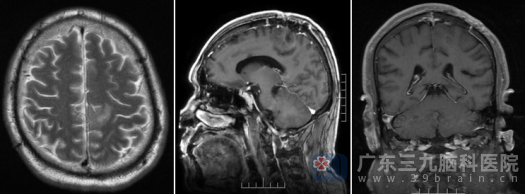

术后影像资料

术后的病理结果揭开了谜底: (左侧额叶肿瘤)少突胶质细胞瘤, IDH突变并1p/19q共缺失,组织学WHO 2级。 这是一个相对低级别的恶性肿瘤,但因其位于功能区,早已引起了局部的神经功能障碍-导致右侧肢体麻木无力。

目前,周大爷术后恢复良好,神志清醒,对答切题,四肢活动自如。下一步,他将转至肿瘤科,接受进一步的放化疗,以最大程度地防止肿瘤复发。